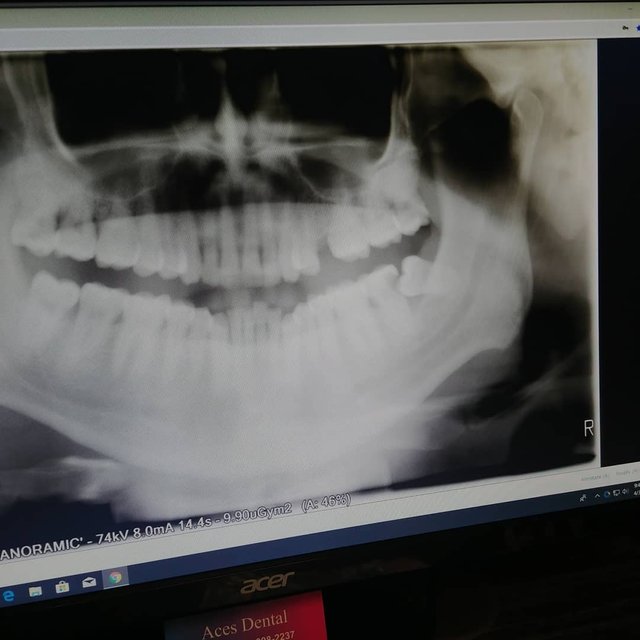

Funny how during my most stressful and most transitional period of my life, I have a #wisdomtooth lodging itself in the most impossible way into my molar. Having union insurance didn't help the situation as it was never covered this when it became an issue. Now I need emergency surgery and Medicare has me waiting a week for a emergency surgery.

The pain is unreal. Luckily, through persistent diet and exercise I have had a much better prognosis on my mouths 'cleanliness'. The last Dentist I went to 3 years ago said I needed a full cleaning possibly 2 😲😬😅. Hopefully the Oral Surgeon agrees and that Gidget our family dog will take care of me after the surgery as she is the only reason I was able to move back. She is a old dog with a heart of gold... #orthopedicsurgery #fml #dentist #pain #lotsofpain #anxiety #share2steem #steemit